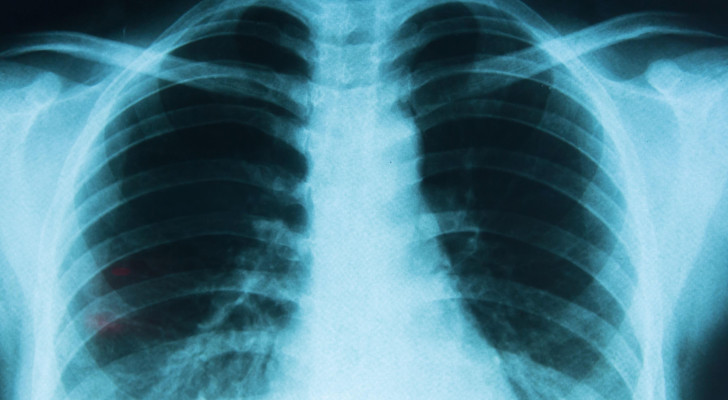

سرطان الرئة يهدد غير المدخنين.. العلماء يكشفون السبب الصادم!

تشير دراسات حديثة إلى تزايد ملحوظ في حالات الإصابة بسرطان الرئة بين الأشخاص غير المدخنين، ما دفع علماء إلى تصنيفه كنوع مستقل من السرطان، يختلف في خصائصه عن السرطانات المرتبطة بالتدخين التقليدي، ويظهر غالبا لدى فئة عمرية تتراوح بين 30 و35 عاما.

ويعد السرطان الغدي أحد أكثر الأنواع شيوعا في هذا السياق، وهو نوع من السرطان يبدأ في الغدد المسؤولة عن إفراز المواد المخاطية أو السوائل داخل الجسم، ومن أبرز التحديات المرتبطة به أن أعراضه غالبا لا تظهر إلا في مراحل متقدمة، بعد انتشار الورم، وتشمل السعال المستمر وألم الصدر وضيق التنفس.